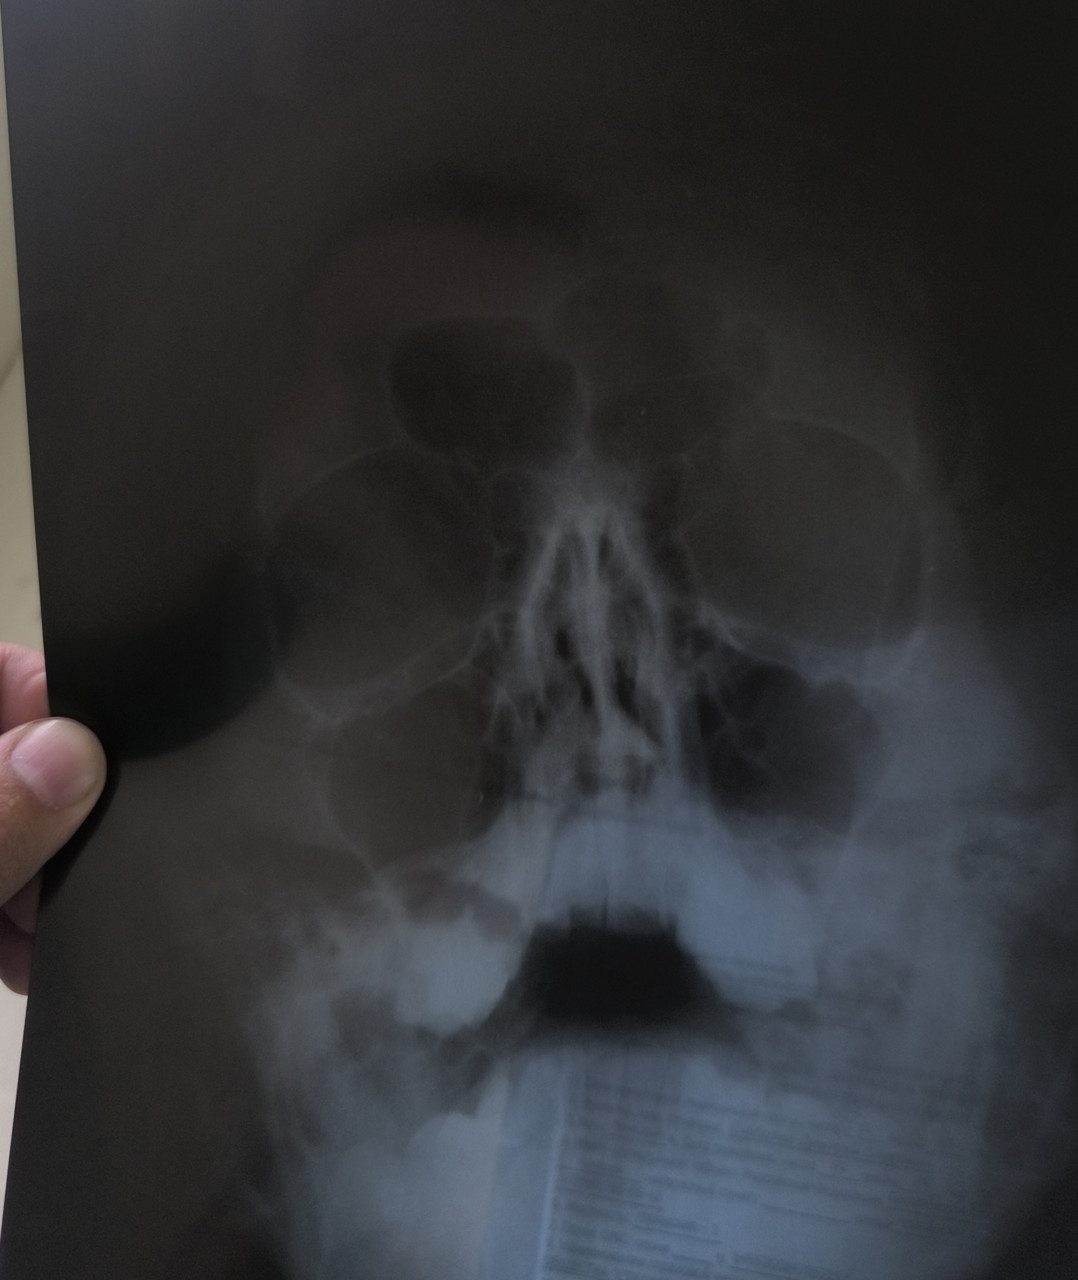

Здравствуйте! Можете сказать по рентгену есть искривление носовой перегородки? Или так называемый шип? Стоит делать операцию? И каким методом его будут удалять?

Здравствуйте. По снимку видно искривление носовой перегородки и вероятно наличие шипа. Решение о необходимости операции зависит от выраженности симптомов таких как  затруднение дыхания, хронический ринит. Метод удаления выбирает оперирующий ЛОР после очной консультации и КТ.